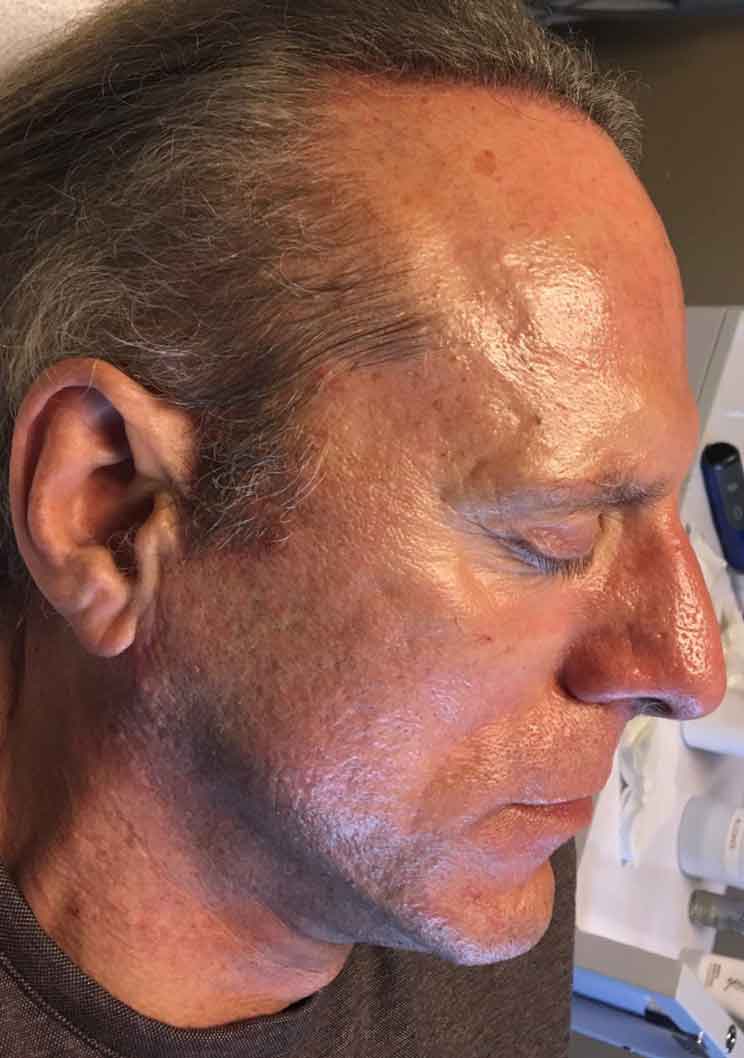

This patient came to our master estheticians to look into acne scar treatment. Her master esthetician recommended the Glow Up Package. The patient underwent her first microneedling session and has already seen amazing results.

See how microneedling treatments can improve skin texture and tone on our Microneedling procedure.